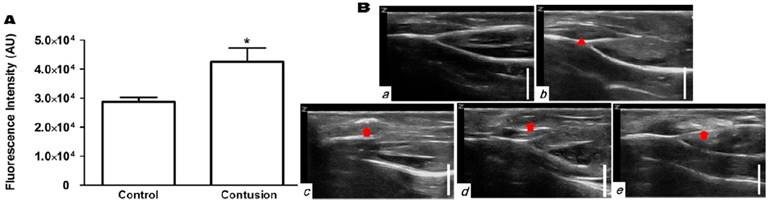

Ultrasonographic imaging of contusion injury

To test whether the H2O2-triggered echogenic properties of PVAX nanoparticles translates to the in vivo setting, we investigated the potential of PVAX nanoparticles as ultrasound contrast agents using a rat model of contusion injury. As PVAX nanoparticles were designed to generate the echo signal in a H2O2-triggered manner, we first investigated the level of H2O2 in the contusion injury of muscles. Figure 3A illustrates the level of H2O2 in muscles before and 6 h after contusion injury, determined by Amplex Red assay. Injured triceps surae muscles exhibited more than 2-fold higher level of H2O2 compared to the non-injured tissues. These results clearly demonstrate that the level of H2O2 is significantly elevated during the contusion injury of muscles.

Figure 3

Ultrasonographic imaging of skeletal muscles. (A) Determination of the level of H2O2 in skeletal muscles before and after contusion injury. Tissues were collected at 6 h post-contusion injury and the level of H2O2 in tissue lysates were determined using Amplex red assay. **p<0.01. Data are mean ±s.d. (n=4). (B) Ultrasonography of muscles with contusion injury obtained using various ultrasound contrast agents. Ultrasonographic imaging was obtained immediately after injection of contrast agents. a) No contusion. b) Contusion only, c) Contusion + PVAX nanoparticles, d) Contusion + PLGA nanoparticles, e) Contusion + SonoVue. An arrow-head indicate the contusion site. Arrows indicate the ultrasonographic imaging effect by injectants. (C) Time courses of ultrasonography of contusion injury using PVAX nanoparticles. The syringe needle was placed into the muscles near injured site (white arrow) and PVAX nanoparticles were injected. After the injection of PVAX nanoparticles, significantly enhanced ultrasonographic contrast was observed immediately around the injected area (arrow). Then, the hyperechoic PVAX nanoparticles were observed in the injured area (arrow-head) at ~10 sec after injection and they exhibited remarkable contrast enhancement in the injured site. The scale bar is 5 mm. Data are representative of three independent experiments.

We further evaluated the diagnostic potential of PVAX nanoparticles using a rat model of Achilles tendon injury. Contusion injury significantly (~50%) elevated the level of H2O2 in Achilles tendons (Figure 4A). The normal tendons exhibited thin, fine and tightly packed linear echo textures (Figure 4Ba). In a group of rats with Achilles tendon injury, the swelling of Achilles tendon was observed, but the injury had indistinct appearance (Figure 4Bb). PLGA nanoparticles directly injected into tendino-muscular junction exhibited no distinct ultrasonographic contrast in the injury site (Figure 4Bd). However, PVAX nanoparticles directly injected exhibited significantly elevated echo signal only in the injury site (Figure 4Bc and Figure S3). SonoVue also exhibited significantly enhanced ultrasonographic contrast in a widespread area surrounding the injection site (Figure 4Be), a different pattern from PVAX nanoparticles.

Ultrasonographic imaging of Achilles tendons. (A) Determination of the level of H2O2 in Achilles tendon before and after contusion injury. Tissues were collected at 6 h post-contusion injury and the level of H2O2 in tissue lysates were determined using Amplex red assay. *p<0.05, Data are mean ±s.d. (n=4). (B) Ultrasonographic images of contusion injury in Achilles tendon using various ultrasound contrast agents. Ultrasonographic imaging was obtained after immediately after injection of contrast agents. a) No contusion. b) Contusion only, c) Contusion + PVAX nanoparticles, d) Contusion + PLGA nanoparticles, e) Contusion + SonoVue. Arrow-heads indicate the contusion site. Arrows indicate the ultrasonographic imaging effect by injectants. Data are representative of three independent experiments. The scale bar is 5 mm.